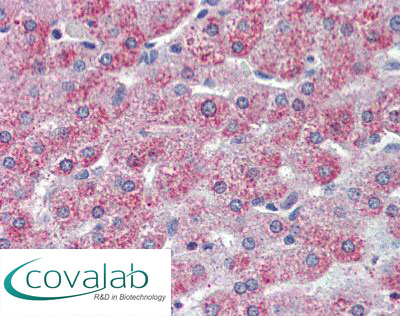

Anti-TAOK1 antibody IHC staining of formalin-fixed, paraffin-embedded human liver after heat-induced antigen retrieval.

Anti-TAOK1 antibody IHC staining of formalin-fixed, paraffin-embedded human liver after heat-induced antigen retrieval.